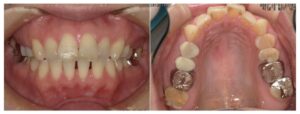

⑤ 矯正の経過写真

矯正開始前と最新のお写真を掲載しています。

実際の変化が伝わりやすいので、ぜひご覧ください。

Before